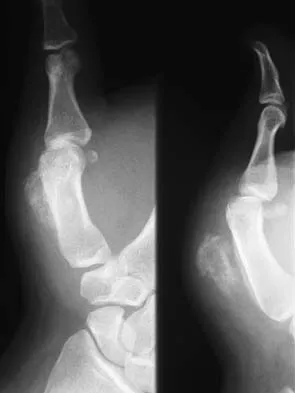

Figures 22a and 22b show the radiographs of a patient who reports stiffness of the hip and associated pain. Management should consist of

The patient has grade IV heterotopic ossification with the limb in an abnormal nonfunctional position. Treatment should consist of excision of the bone to restore hip motion and prophylaxis to prevent recurrent formation. The best time to excise the bone is controversial, with no conclusive evidence supporting early or late excision. Pellegrini VD Jr, Koniski AA, Gastel JA, Rubin P, Evarts CM: Prevention of heterotopic ossification with irradiation after total hip arthroplasty: Radiation therapy with a single dose of eight hundred centigray administered to a limited field. J Bone Joint Surg Am 1992;74:186-200.

- Warren SB, Brooker AF Jr: Excision of heterotopic bone followed by irradiation after total hip arthroplasty. J Bone Joint Surg Am 1992;74:201-210.